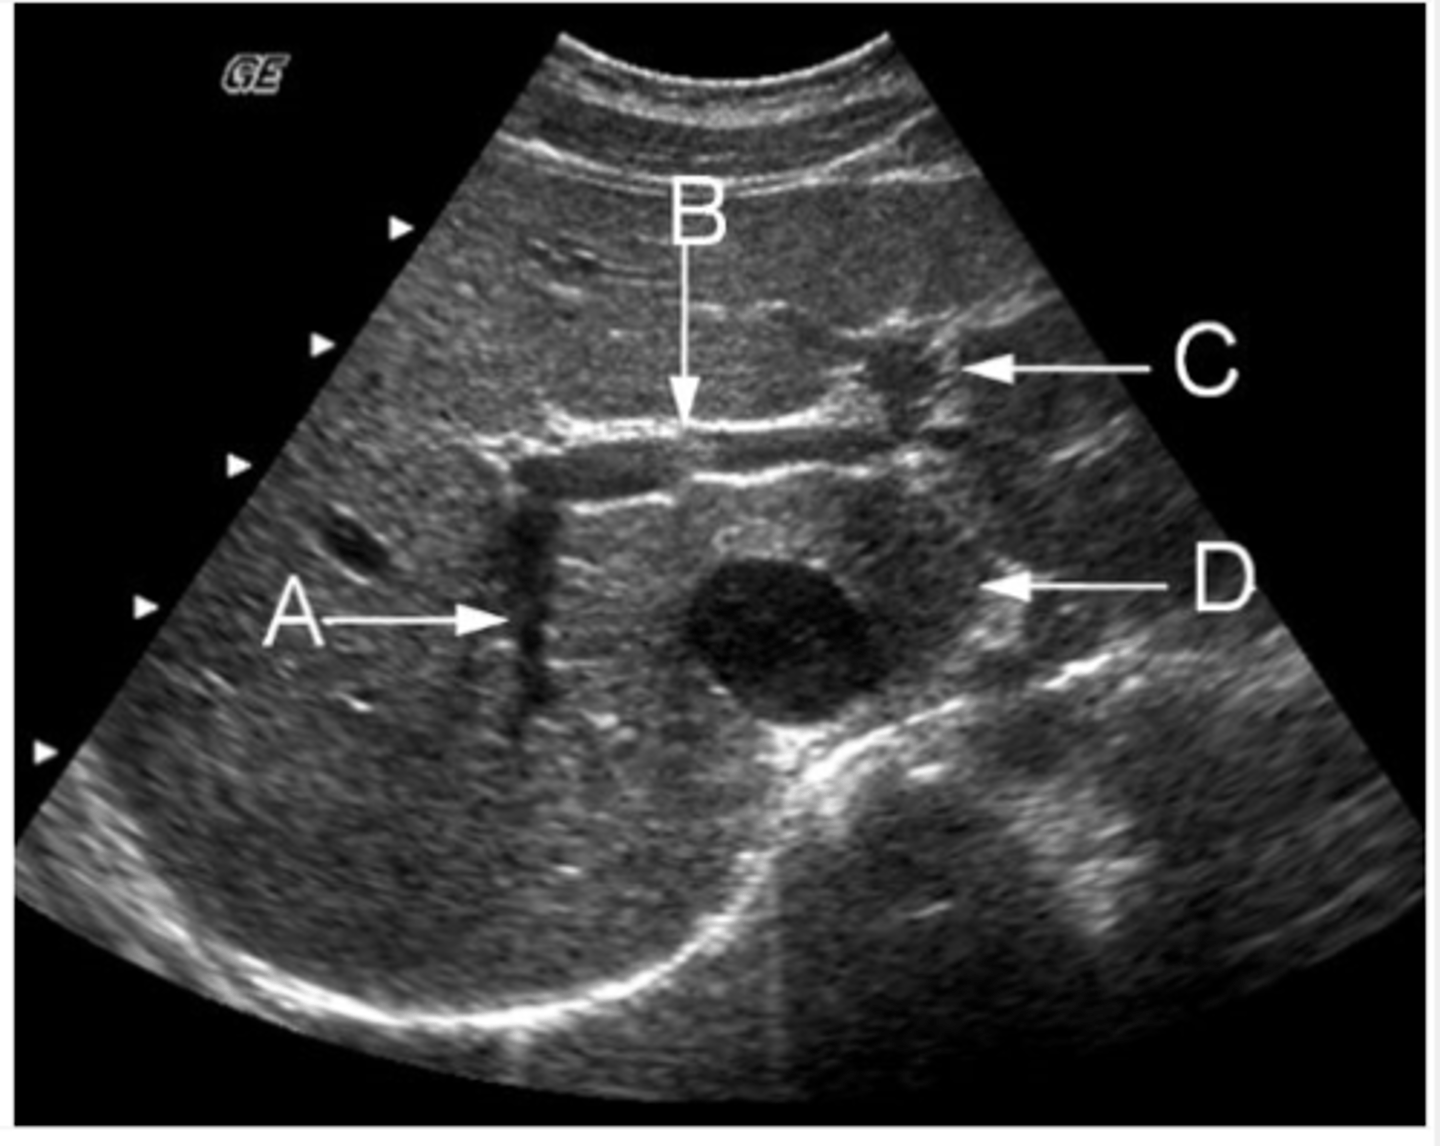

d. abdominal aortic aneurysm and horseshoe kidneys

This transverse image was obtained in the mid abdomen of a 57- year-old male with lower back pain. Which of the following correctly describes the sonographic findings?

a. leaking abdominal aortic aneurysm with hematoma

b. abdominal aortic aneurysm and para-aortic lymphadenopathy

c. inflammatory abdominal aortic aneurysm

e. abdominal aortic aneurysm with retroperitoneal fibrosis